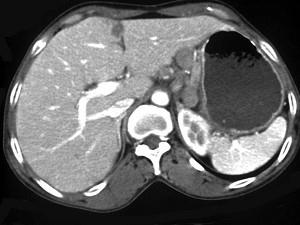

问题 女,56岁,上腹部钝痛、腹胀不适一月余,纳差、消瘦,影像检查如图,最可能的诊断是 ( )

选项 A、胃间质瘤 B、胃恶性间质瘤 C、胃腺癌并幽门狭窄 D、胃淋巴瘤 E、胃幽门管溃疡

答案 C